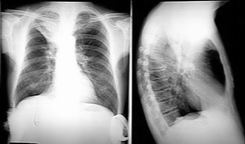

| Prior imaging | oldest & most recent |

| Technical quality | Rotation (spinous processes equidistant from medial end of clavicles)

Inspiration (6 - 7 anterior ribs in MCL) Penetration (spinous processes visible) |

| Abdomen | Diaphragm, pneumoperitoneum, colonic interposition, costophrenic angles, subpulmonic effusion (highest point of hemidiaphragm displaced laterally), tension pneumothorax |

| Thoracic cage | #'s, lesions, notching, pneumothorax |

| Mediatinum | Heart (size, contour), great vessels, airways, esophagus, LN's, AP window, paratracheal stripe, paraspinal lines, ant & post junction lines, azygoesoph recess |

| Lung parenchyma | CPA, apices, volumes, vascular markings, lesions (including behind heart & diaphragm), pneumothorax |

Lateral: diaphragm, CPA, spine sign, hilar LAD, posterior wall of bronchus intermedius, upper lobe bronchi, retrosternal space